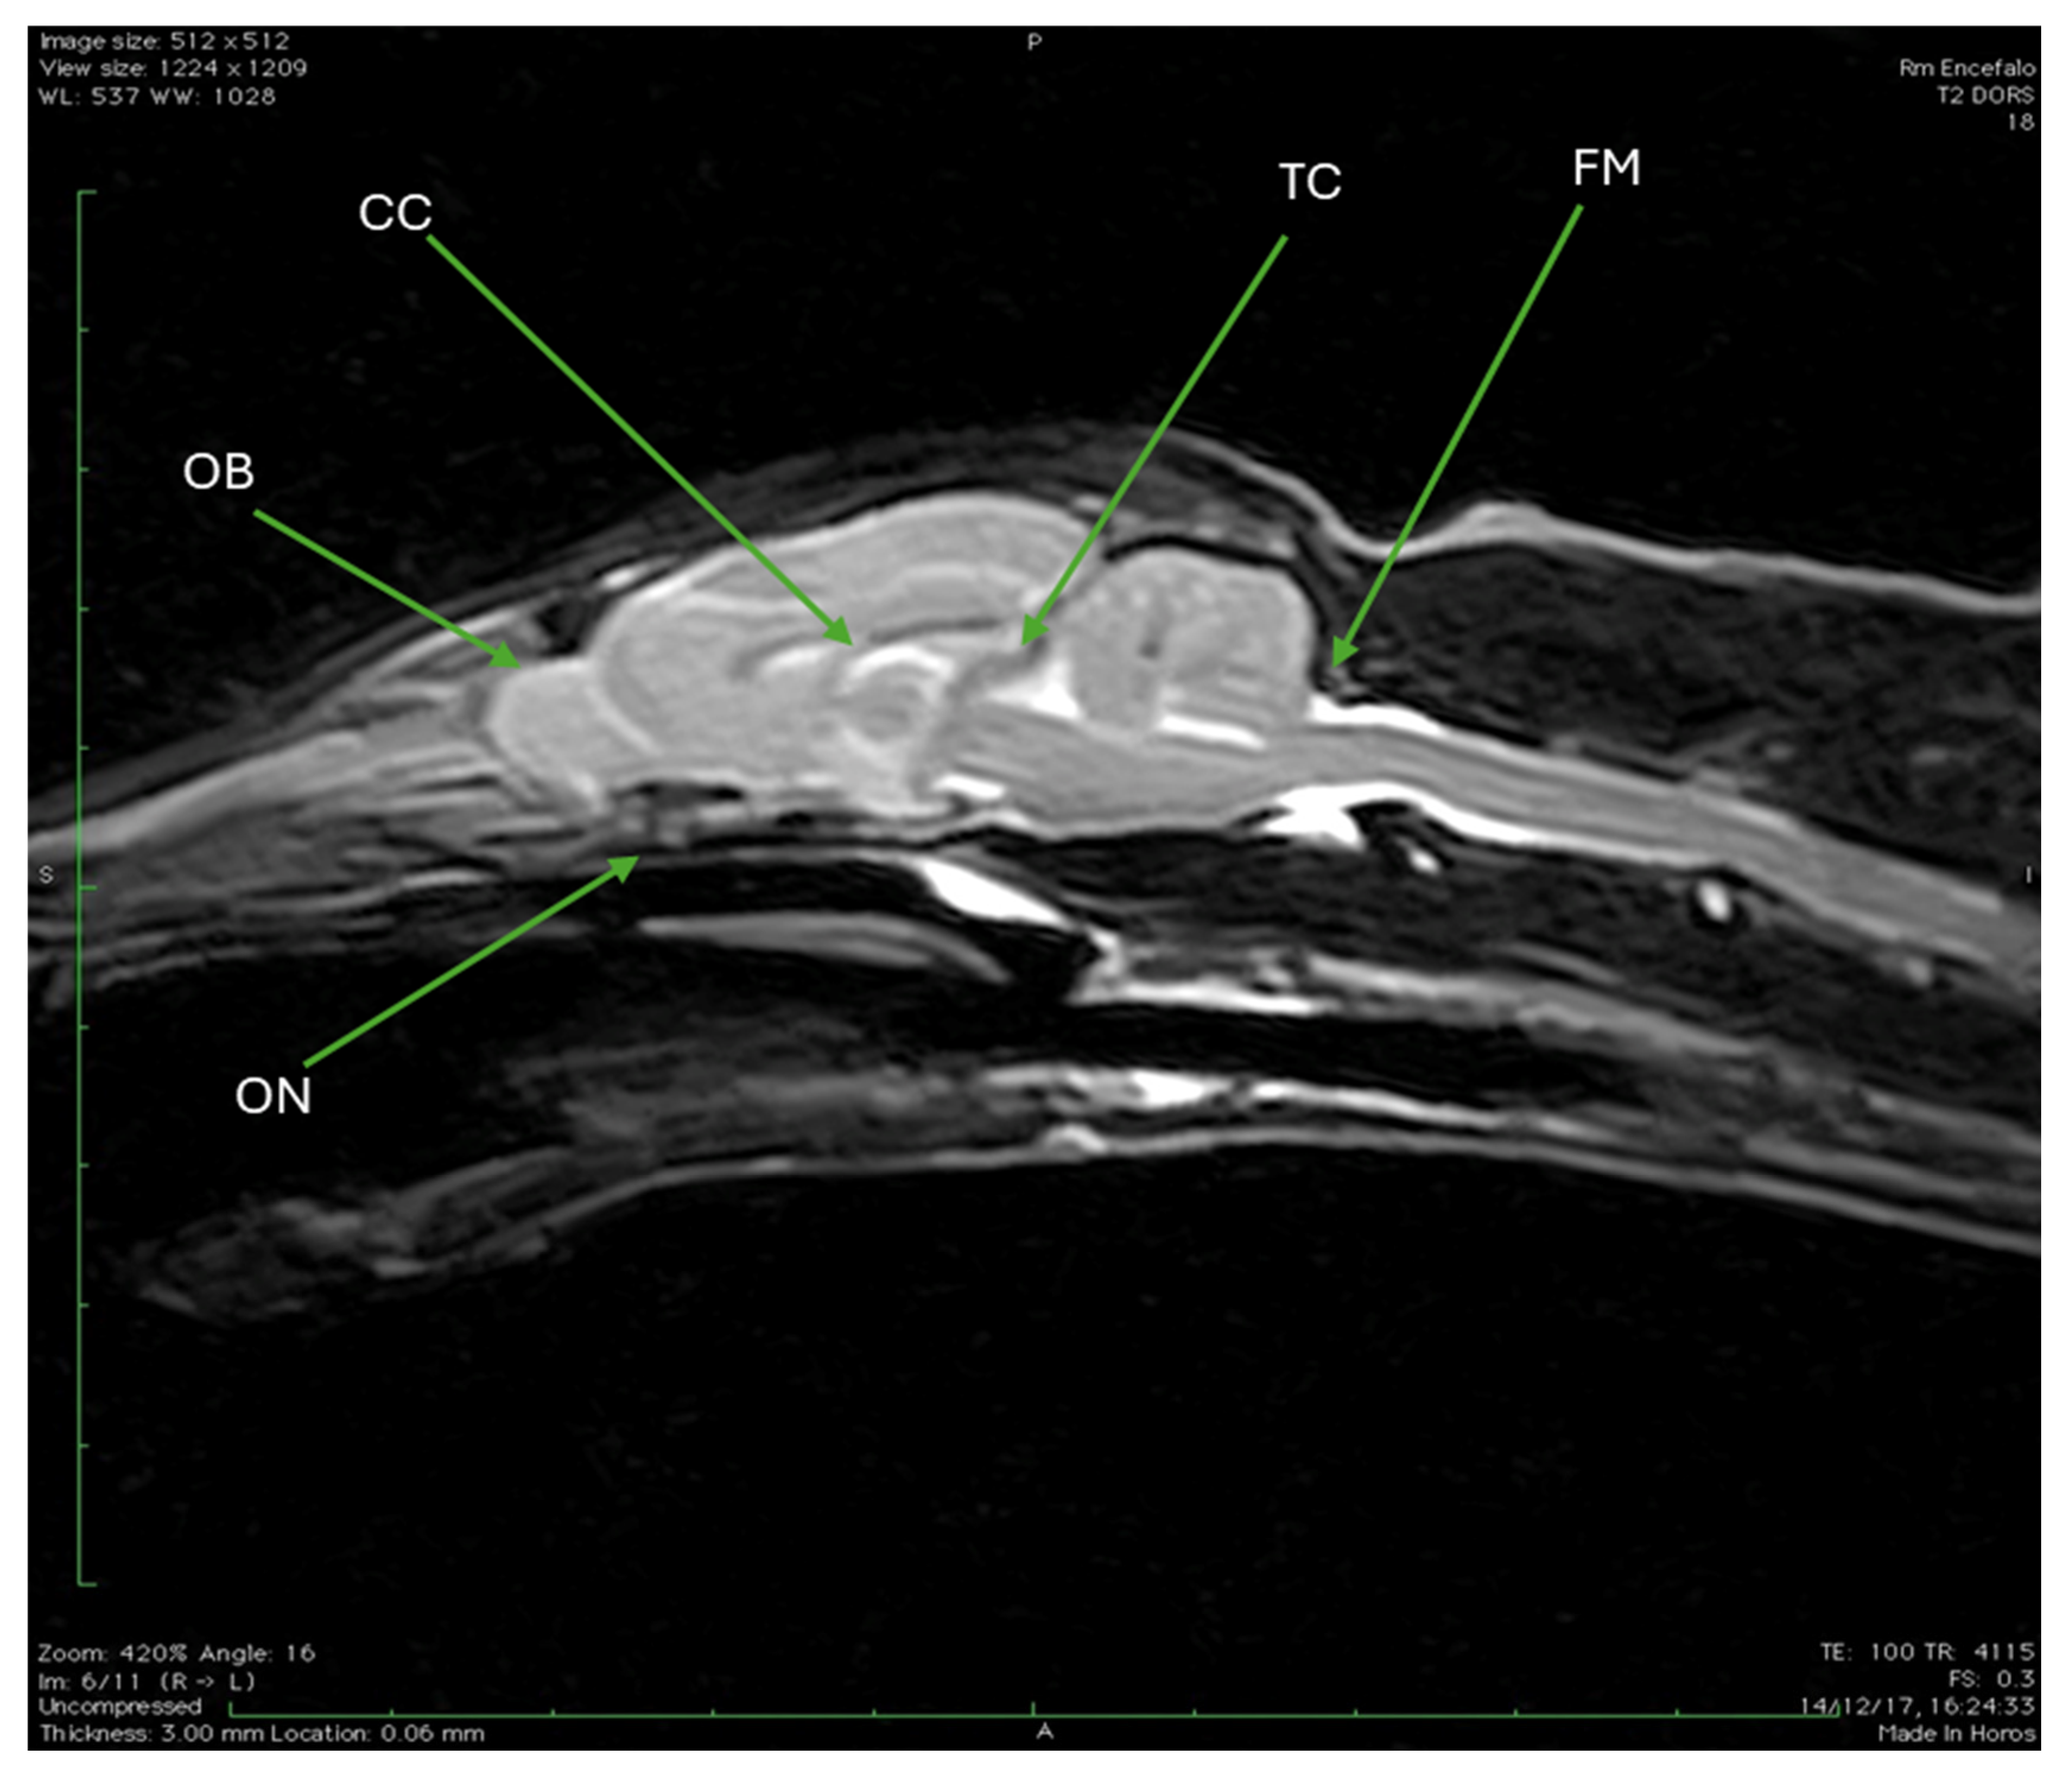

| CC | Corpus callosum |

| OB | Olfactory bulb |

| ON | Optic nerve |

| TC | Tentorium cerebelli |

| FM | Foramen magnum |